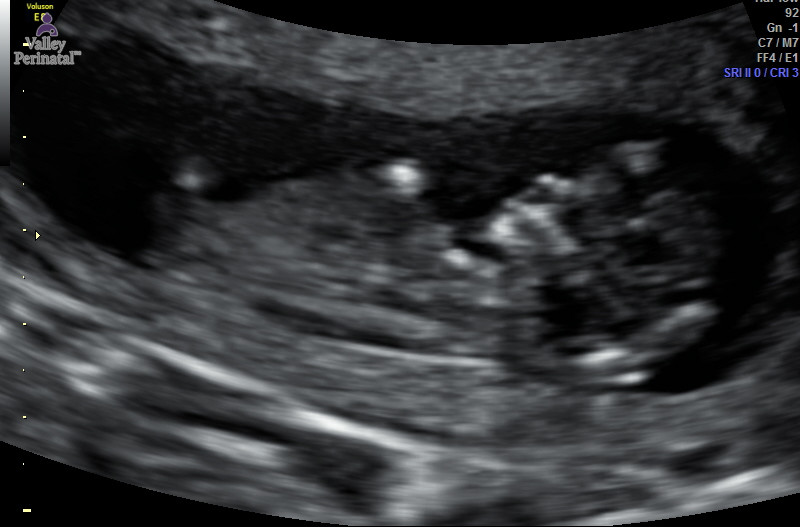

I had the gender experts do a prediciton they said girl, the Tech said girl too she thinks pink.. that is what I am hoping for I have 2 boys.. what do you guys think? I lso attatched one for skull theory from the same ultrasound? WE are goinga t 14 almost 15 weeks for an elective scan the picture was 12w 4d

Attachment 30220

The tech thought girl based on what she thought nub and the potty shot showed absolutely nothing

Hard to see the nub but i think girl.